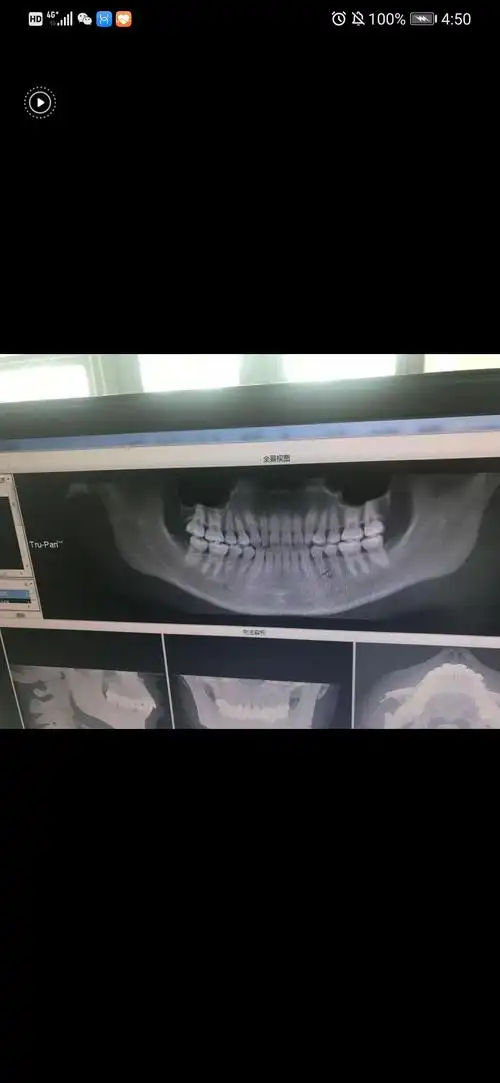

给大家看看我的牙片

求友友们看看我的牙片吧